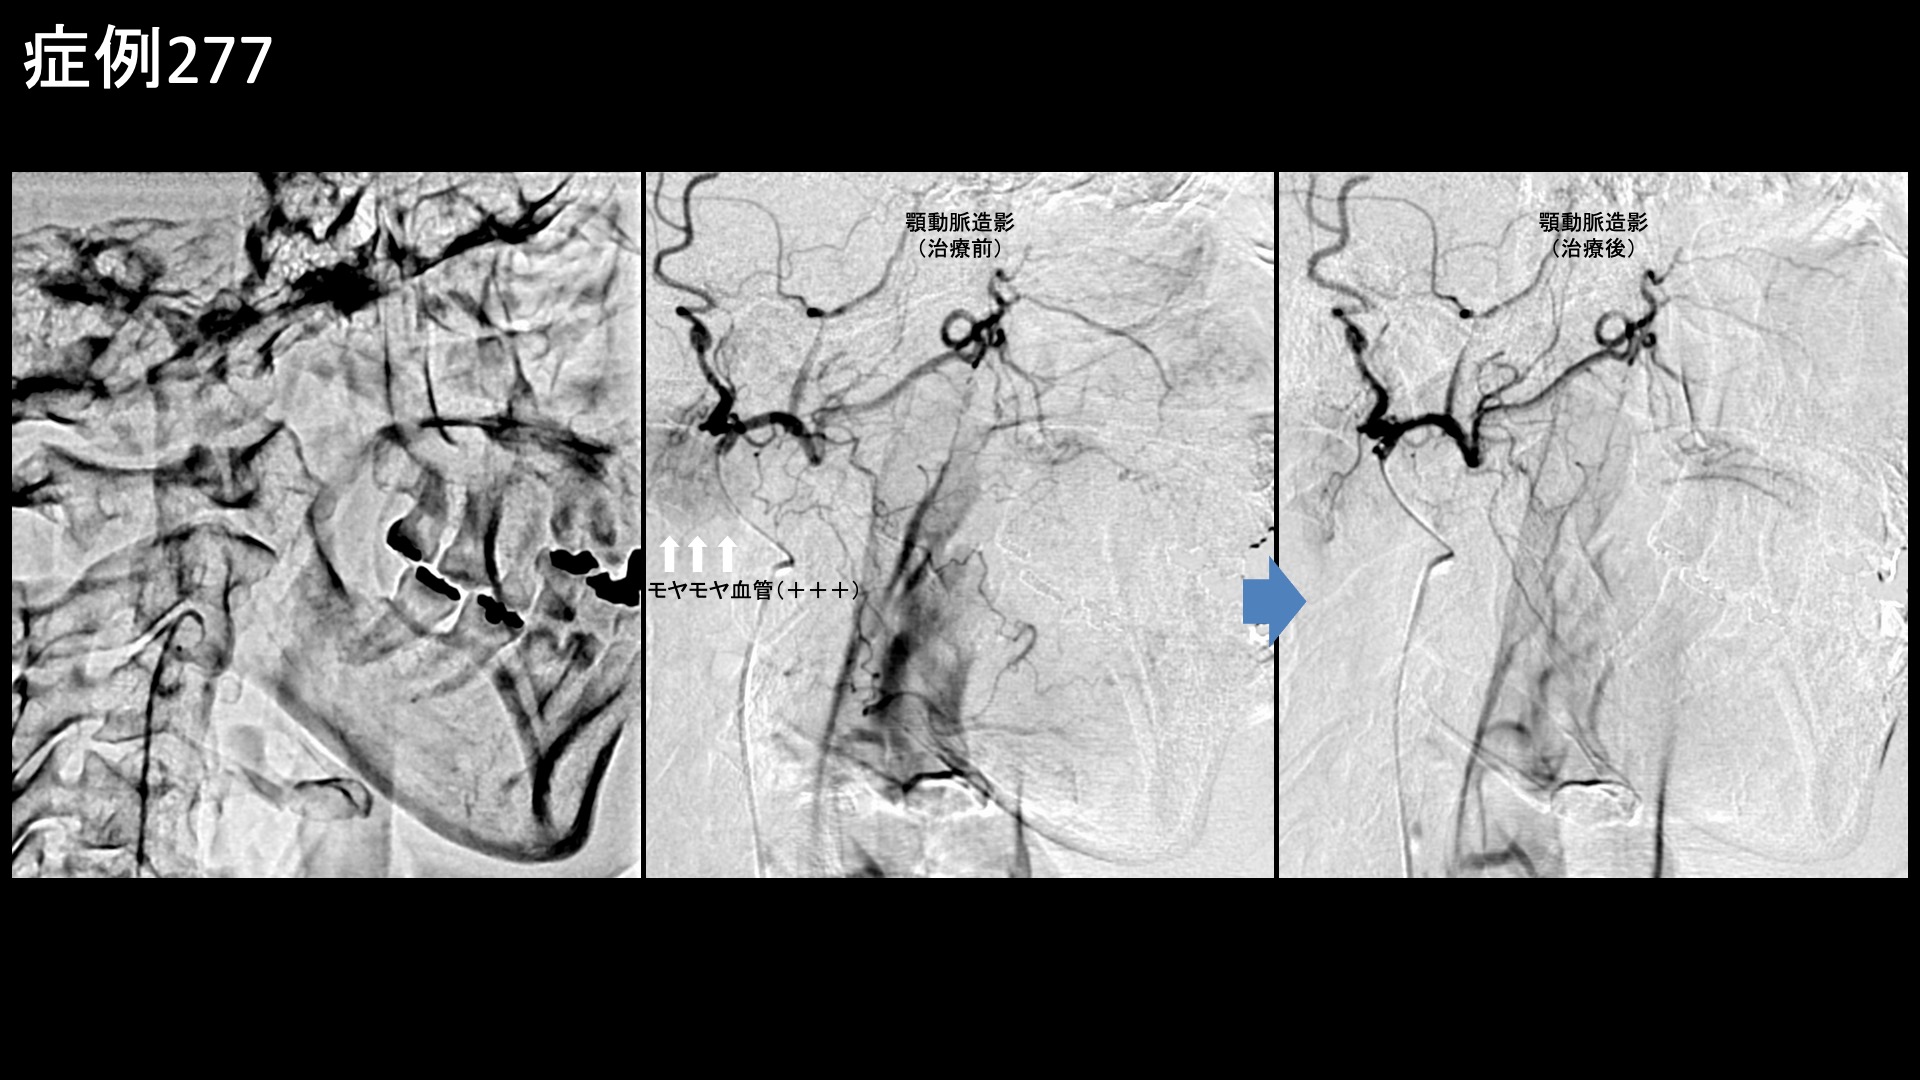

顔:頭痛など 【60代:女性】コロナ禍で急増した顎関節症(mask related TMD)はモヤモヤ血管治療で解決!顎関節症に対するカテーテル治療(顎関節症、コロナ禍、mask related TMD) 2026.04.07 鴨井院長による動画解説 受診までの経過 1年8ヶ月前から、朝起きたときに顎のズレを感じるようになりました。次第に、顎関節を中心として右耳の前方から下顎、さらには首肩まで痛むようになりました。痛みは起床後から寝るまで四六時中続き、歯科でマウスピース治療を受けましたが、治りませんでした。当院の治療を知り受診されました。 診察時の所見 首肩こりは元々なく、首肩の痛みはあくまでも顎関節症から波及しているとのことでした。診察上も特に問題ありませんでしたので、治療は顎関節のみに行うこととしました。顎関節症はモヤモヤ血管治療の適応疾患ですので、モヤモヤ血管(病的新生血管)に対する運動器カテーテル治療(微細動脈塞栓術)を受けていただきました。 治療の所見 顎関節に直接関係はしないものの、関連する筋・筋膜性疼痛を引き起こすため顔面動脈の治療は必ず行います。顔面動脈はモヤモヤ血管がよく描出される血管の一つです。血管造影を行うと、モヤモヤ血管が濃染像として豊富に描出されました。治療後は画像上速やかに消失しました。顎動脈でも、一定のモヤモヤ血管が同様に描出されました。治療時にはそれぞれ再現痛も確認できました。その他複数個所の治療を行い終了しました。 *再現痛とは、薬液投与時に普段の痛みが一定程度再現される現象です。責任血管の同定のための参考とします。 治療前画像:損傷を受ける、あるいは繰り返しのストレスにより発生した異常な新生血管 治療後画像:カテーテルを用いて塞栓物質を血管内に投与し新生血管を塞いだ状態 治療費用:治療する部位によって費用が異なりますのでこちらをご参照ください。 主なリスク・副作用等:針を刺した場所が出血により腫れや痛みを生じたり、感染したりすることがあります(穿刺部合併症)。造影剤によるアレルギー(皮膚のかゆみ・赤み・息苦しくなるなどの症状)が出ることがあります。 治療後の経過 治療直後から症状が改善しました。治療後1ヶ月の再診時には痛みが消失し、圧痛も無くなっていました。非常に経過良好であり終診となりました。 顎関節症はモヤモヤ血管が深く関わっている代表的な疾患の一つであり、治療後は他疾患よりも比較的早期から改善することが多いです。顎関節症はマスク生活により増加したと指摘されており、mask related TMDという言葉があるほどです。マスク関連性のTMD ;Temporomandibular Joint Disorder、顎関節症ということです。顎関節症にとっては、上下の歯列が接触する機会が増えることが最大の増悪因子なのですが、マスク生活ではまさにそうなるからです。ひどくなると、頭痛や首肩こりの原因にもなります。モヤモヤ血管治療の良い適応疾患ですので、お悩みの方はご検討いただくと良いかと思います。 顎関節症の詳細はこちら 【60代:女性】肩の激痛も石も消滅!石灰沈着性腱板炎に対する運動器カテーテル治療(石灰沈着性腱板炎、肩関節周囲炎) 前の記事